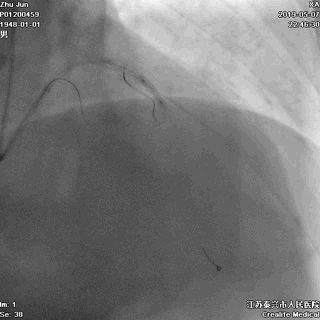

五、高压后扩张

---保证STENT充分贴壁

非顺应性球囊高压后扩,保证STENT充分贴壁

六、主干支架近段优化

---不能省略的步骤

大一号球囊高压扩张近段STENT

七、最终结果

---即刻效果完美

手术即刻效果完美,患者存活